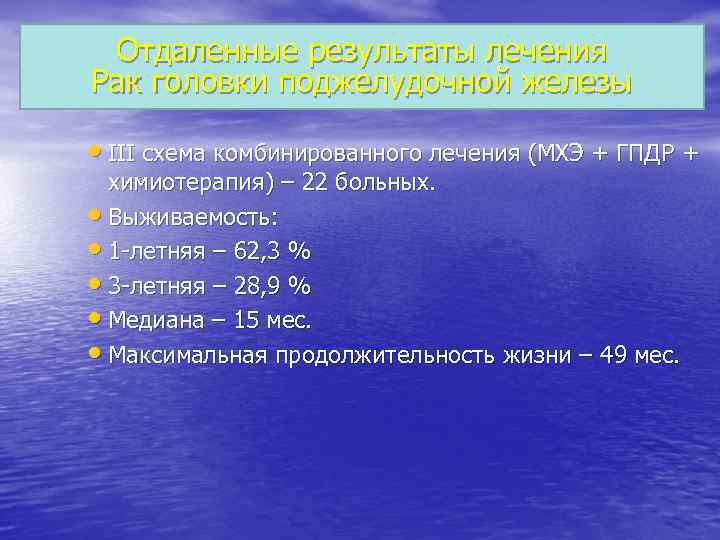

Отдаленные результаты лечения Рак головки поджелудочной железы III схема комбинированного лечения (МХЭ + ГПДР + химиотерапия) – 22 больных. Выживаемость: 1 -летняя – 62, 3 % 3 -летняя – 28, 9 % Медиана – 15 мес. Максимальная продолжительность жизни – 49 мес.